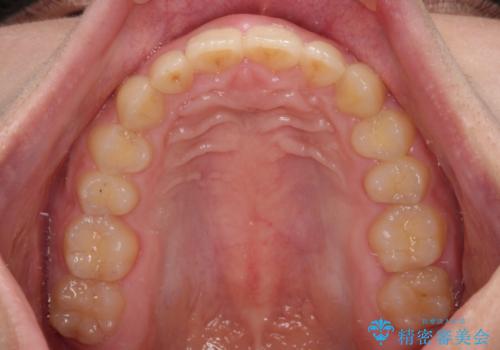

- 深い咬み合わせと上顎前歯の突出感を気にして来院された患者様です。

当院では通常、臼歯の咬合が理想的な位置に対して上顎が前方位にある場合。ワイヤー矯正または補助装置の併用したインビザライン矯正を選択しています。

今回は、できるところまででいいのでインビザライン単体で治療をしたいという希望があったため、インビザラインにて矯正治療を行うこととしました。

正面や横からの写真ではきれいに治っており、患者様は大変満足のいく仕上がりとなりましたが、深い咬み合わせの改善は不十分で、奥歯の咬み合わせも改善させることができませんでした。

インビザラインは、咬合力の強い方ですと、奥歯が歯肉内にめり込んでしまうため、前歯が強く接触してしまうことがあります。

こちらの方は、奥歯はしっかりと噛んだのですが、歯肉にめり込んでしまったことで、歯肉が腫れやすくなってしまいました。